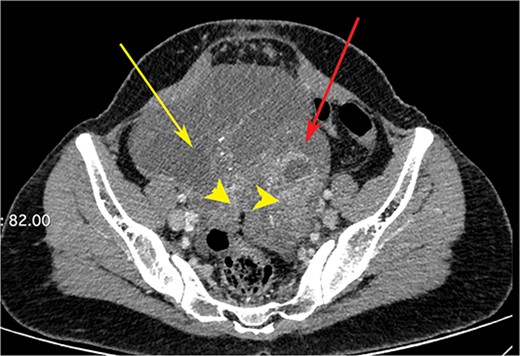

CT scan of the abdomen showing gastric wall thickening at the level of the pyloric antrum (yellow arrows).

CT scan of the abdomen showing right ovarian cyst (yellow arrow), left ovarian cyst (red arrow) with solid elements within (arrow heads).